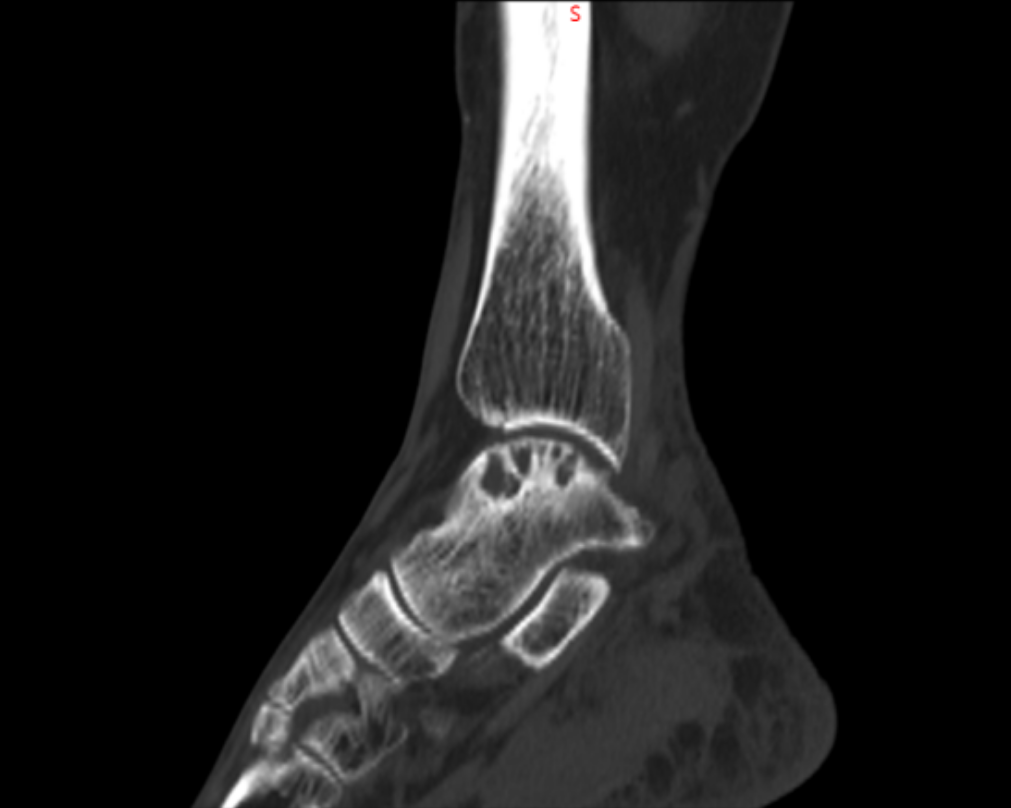

北京积水潭医院郑州医院、郑州大学附属郑州中心医院足踝外科李恒的诊室,李恒指着片子解释距骨内侧出现囊性变,这确实是棘手的问题。由于内部压力大,不但会疼痛,还有可能引起距骨塌陷骨折。我抢答:能不能不换踝关节?我还年轻,而且换踝关节费用太高了。

踝上截骨治疗踝关节关节病及距骨骨软骨损伤的手术治疗,对医生手术技术要求高,需要对踝足部的力线及平衡调整有丰富临床经验,术中要有很强应变能力。在李恒和足踝外科小组配合下顺利完成!

术后复查X线,非常完美。李恒提醒,踝关节是人体中负重最大的关节,出现问题会给生活带来极大的痛苦和不便,崴脚并非小事,若早期处理不当,错过最佳治疗时机,轻则遗留慢性疼痛,重则导致创伤性关节炎、慢性踝关节不稳等后遗症,所以“走路看路”+“积极的运动锻炼”,预防踝关节损伤非常重要!